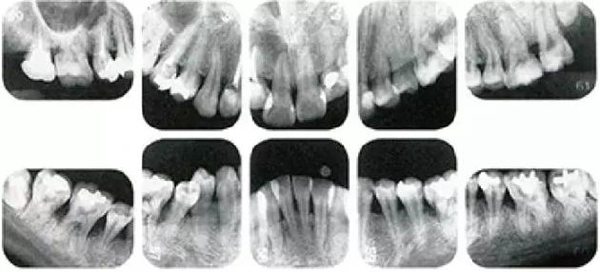

牙周病的發(fā)展因部位不同而發(fā)展程度不同的。10點(diǎn)后的狀態(tài)參考病例①和參考病例②的磨牙處的狀態(tài)相比較,思考下沒(méi)接受治療病情發(fā)展的特別性吧。

參考病例① 35歲女性

在左下第一磨牙在25歲時(shí)近中處可以看到垂直性的骨吸收,但35歲時(shí)吸收停止,原本沒(méi)有見(jiàn)到的遠(yuǎn)中處骨吸收的,現(xiàn)在卻吸收得很?chē)?yán)重。

在右下處,原本有大量骨吸收的第一磨牙處的吸收卻變緩慢,原本沒(méi)有吸收的第二前磨牙卻出現(xiàn)了吸收。出現(xiàn)吸收的左上第一磨牙的遠(yuǎn)中處,吸收得越來(lái)越多了。

把10年間的變化做成表格。牙周病的發(fā)展根據(jù)各個(gè)人會(huì)不同,即使通一個(gè)人,不同牙齒,不同牙面發(fā)展的狀態(tài)也不同。